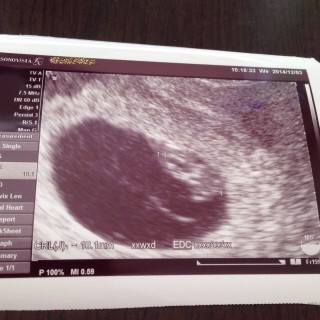

2週間振りの病院でちゃんと大きくなってるかドキドキでしたが、無事大きくなってました♡赤ちゃんの上にあるのは卵黄嚢。 順調ですね!との一言と、予定日決めちゃいましょう!と言われ、予定日は2/20になりました! これから楽しみだなぁ~

頭と胴と手が確認できて、心臓も元気に動いてました。 先生もかわいいね~~7w0dの7.9ミリの倍、15.4ミリまで成長する赤ちゃんはスゴい!と言ってました。

CRL12.0mm